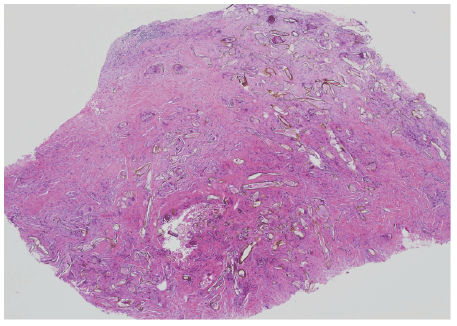

图1:一)一种纤维性结节,点缀着大小不一,形状从黄色到金色细长的膜状宽菌丝状结构。其他呈椭圆形至圆形(苏木精-伊红,原始放大倍数×20)。

组织学上,这些病例的炎症表现为轻度非特异性慢性炎症和明显的混合炎症合并脓肿形成(表2)。纤维化一般较轻。大多数病例显示钙化,从微钙化到大块钙化物质。没有发现类骨形成。3例出血。均无含铁血黄素色素沉积。3例出现不同强度的异物,并伴有异体巨细胞反应。4例未发现异物或异物反应。3例为鳞状上皮,其中2例为穿孔或溃疡的增生性炎症上皮。病例1、4和6显示类似的异物,由大小和形状不等的膜状结构组成(图1和2)。一些是细长的宽壁,另一些是较小的椭圆形或圆形。部分钙化或完全钙化(图1B)。 Foreign body type multinucleated giant cells were seen adjacent to the walls of these structures or “inside” them (Figure 1B). No eosinophils or neutrophils were seen in the vicinity of these structures. We did not find epithelioid granulomas in the case with a history of tuberculosis (case 4) or in the other cases. The walls of the fibers were polarizing. Some showed septated walls arranged in vegetablelike cell chambers. Some of these foreign materials were seen within an abscess or perforating through the surface epithelium with transepithelial elimination (Figure 2). These structures were positive for PAS and GMS (Figure 3). Some sections showed calcified Schistosoma ova-like or Trichuris ova-like structures (Figure 1B).